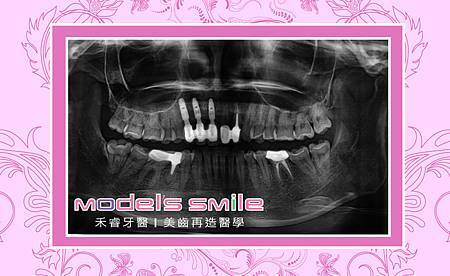

呂睿庭醫師先幫羅小姐做詳細檢查,發現前牙區骨床果真萎縮嚴重,並且細菌侵蝕造成牙根發炎,植牙的條件確實不理想,於是建議先做骨床重建後再進行植牙;也因為考量到羅小姐希望植完牙後能保持美麗與健康,所以再推薦植牙後,以全瓷冠做為膺復以保牙齦健康。

呂醫師運用骨再生術、經劈骨重建術及三合一補骨術,以自體骨骨膠原人工骨粉再加上PRF血小板快速凝結止血,增進骨質再生;經半年骨質重建,接著進行植牙手術,於膺復時再運用雷射做牙齦整型術。前後歷經一年兩個月的時間,終於完成前牙做美感重建。